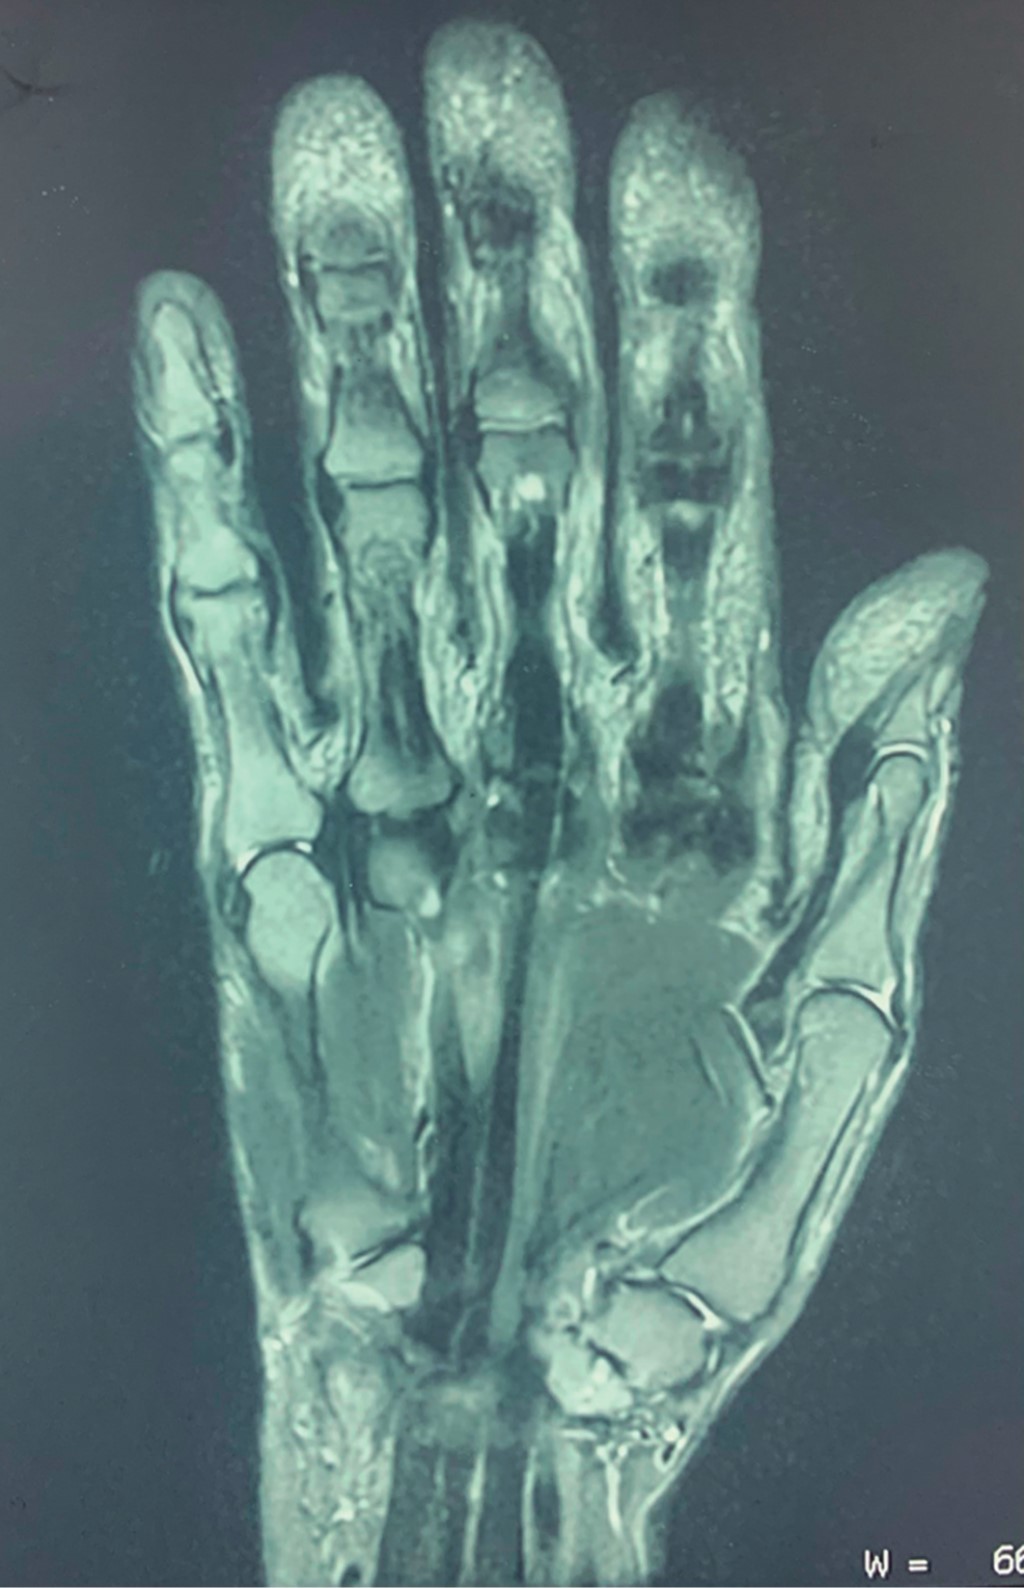

Se trata de mujer de 63 años, de profesión pianista, con diagnóstico acorde con los criterios propuestos por el Colegio Americano de Reumatología de artritis reumatoide, al momento de su valoración en tratamiento únicamente con metotrexato. Refirió iniciar su padecimiento con dificultad progresiva a la extensión de tercer, cuarto y quinto dedo de la mano derecha (Figura 1), los cuales le impiden desarrollar sus actividades de la vida diaria y profesional, motivo por el cual acudió a valoración. Se solicitó estudio de resonancia magnética, el cual evidenció pérdida de la continuidad en tendones extensores correspondientes del tercer al quinto dedo (Figura 2).

Figura 2